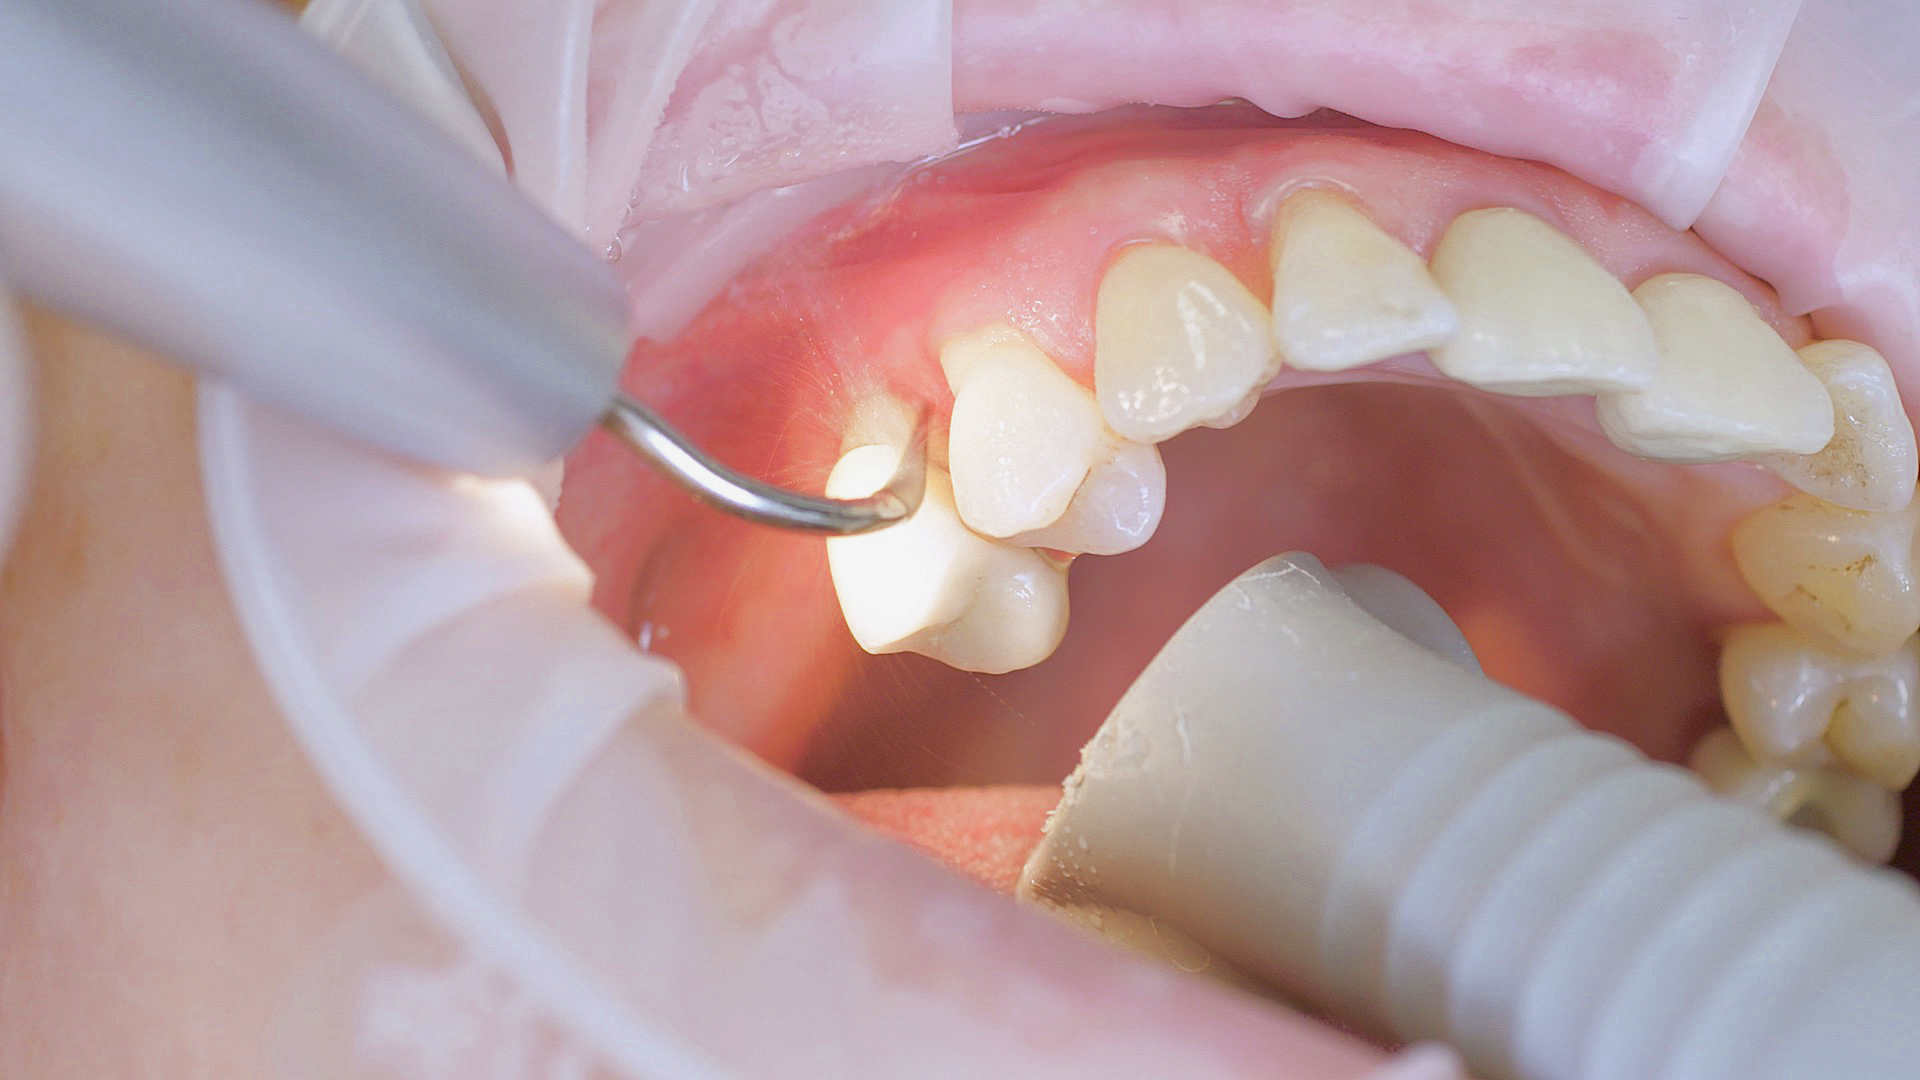

Dans les soins de suivi parodontal post-implantation, les concrétions molles (biofilm) et dures doivent être éliminées régulièrement par des techniques de nettoyage mécanique professionnelles. [16, 17] Dans les zones subgingivales et supragingivales, on utilise généralement pour cela des dispositifs à ultrasons (Fig. 4) en combinaison avec des instruments manuels si nécessaire.

L’aéropolissage subgingival peut également être utilisé, associé à des accessoires parodontaux ainsi qu’à des poudres.[18]